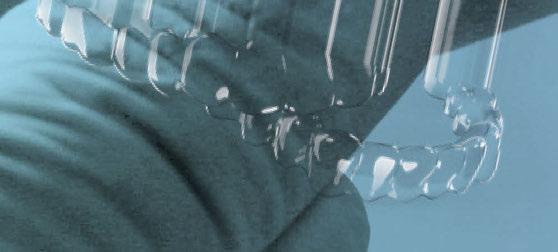

3. Fase quirúrgica final

A los 6 meses de cicatrización, se realizó un nuevo CBCT, obteniendo un nuevo archivo DICOM que alineamos con el STL del encerado. De esta manera, se planificó la posición de los implantes a 4 mm del margen de la restauración final y se diseñó y confeccionó la férula de cirugía guiada dentosoportada en 12-13 y 22-23, la cual imprimimos con la impresora 3D Formlabs®. El provisional

de carga inmediata lo diseñamos con el programa de diseño 3D Exocad® a partir del encerado y se imprimió también en clínica con la misma impresora 3D (Figuras 14-16).